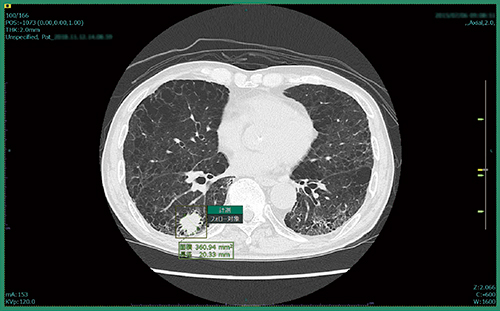

肺結節CADeのプロトタイプは,対象データを開いた時点で,すでに肺結節の検出は完了しており,結果を表示する前に全画像の確認を促すアラートが表示される。検出結果を表示すると,スライス位置を示すインジケーターにも結節が検出された位置が示され,各スライスに直接飛ぶことができる。検出された肺結節は,画像上で縁取りされ,計測結果も表示される(図1)。また,画面内に別ビューアを立ち上げてMPR画像で結節を詳細に確認することができる(図2)。読影者はこれらの情報を参照し,各結節についてフォロー対象とするかを判断することになる。

図2 別ビューア(左)でMPR画像を確認